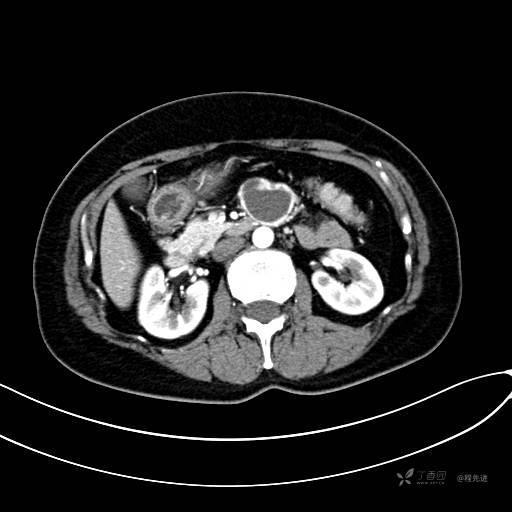

CT增强静脉期